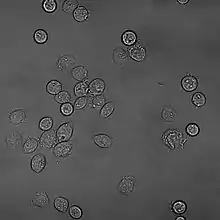

RBL (Rat Basophilic Leukaemia) Cell Line

RBL (Rat Basophilic Leukemia cells)[1] are cancerous basophil cells that are well suited for the study of allergies.[2]

RBL cells are used in allergy studies due to the strong response of the cells to IgE and its FcεRI receptor. They are used in place of mast cells due to a higher stability in tissue culture.[3] RBL cells can also be humanized, aiding in the specificity of allergy studies to human patients.[4]